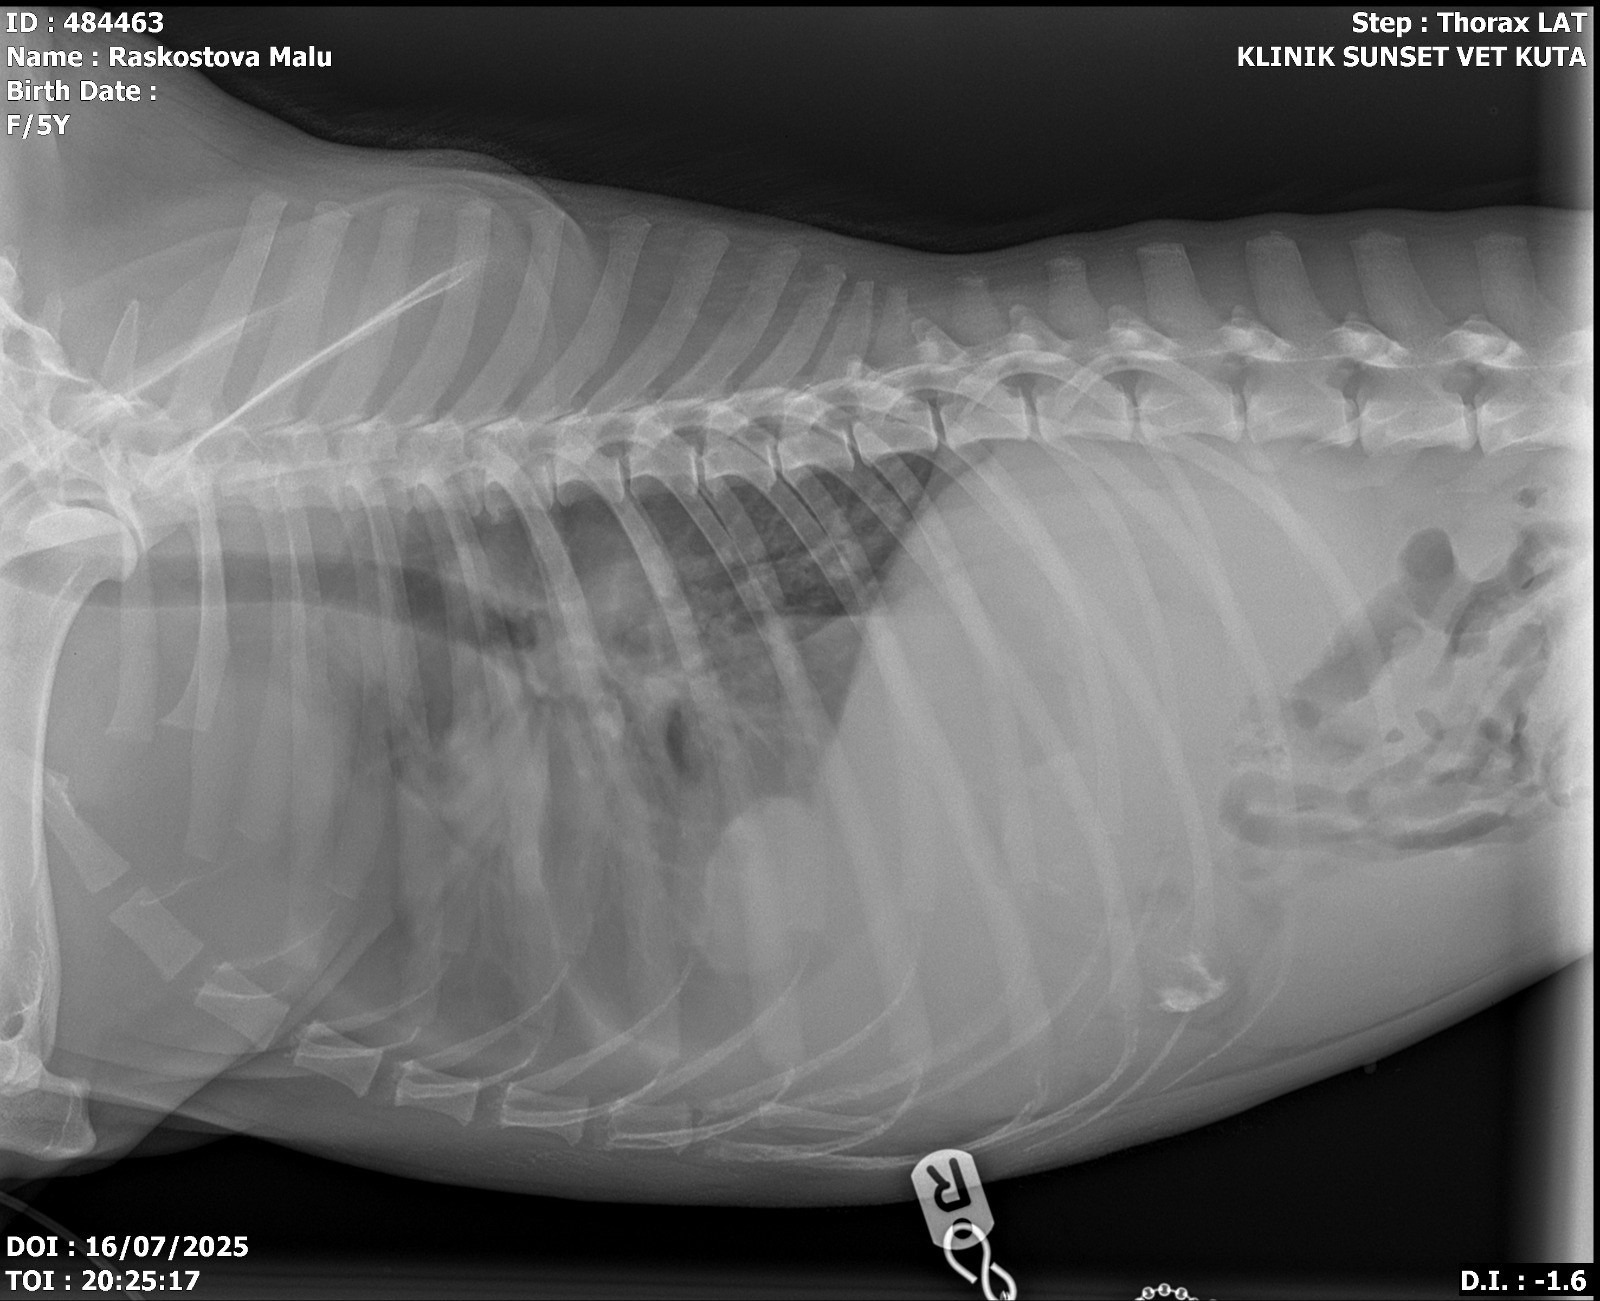

A few weeks ago, Malu’s health began to noticeably deteriorate. She was struggling to breathe, struggled to walk, had stopped eating, and worst of all she had developed a growing lump on her neck. Her feeders stepped in to get her the help she needed, tranquilising her before transporting her to the local vet.

The diagnosis: Lymphoma.

The local vet acted swiftly. The buildup of fluid in her lungs was drained making it easier for her to breath, and medication was immediately prescribed to alleviate the symptoms.